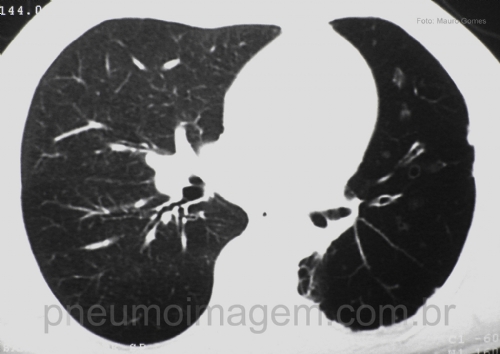

CASO CLÍNICO #3Homem, 28 anos, apresenta-se com dispneia desde a infância, mas que se acentuou no último ano. Apresenta crises de chiado com tosse e expectoração purulenta eventualmente. Ao exame, emagrecido, dispneico, com MV diminuído globalmente e sibilos expiratórios difusos, sem edemas ou cianose. Espirometria com distúrbio ventilatório obstrutivo grave e sem resposta ao broncodilatador.

Man, 28, presents with dyspnea since childhood, but increased in the last year. Shows wheezing episodes with cough and purulent sputum eventually. On examination, weight loss, dyspnea, diffuse expiratory wheezing with no edema or cyanosis. Spirometry with severe obstructive ventilatory disorder and unresponsive to bronchodilators.